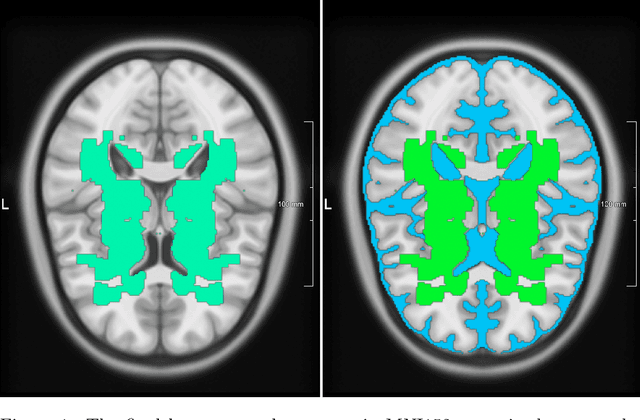

Abstract:We propose the Generalized Probabilistic U-Net, which extends the Probabilistic U-Net by allowing more general forms of the Gaussian distribution as the latent space distribution that can better approximate the uncertainty in the reference segmentations. We study the effect the choice of latent space distribution has on capturing the variation in the reference segmentations for lung tumors and white matter hyperintensities in the brain. We show that the choice of distribution affects the sample diversity of the predictions and their overlap with respect to the reference segmentations. We have made our implementation available at https://github.com/ishaanb92/GeneralizedProbabilisticUNet

Abstract:We propose the Generalized Probabilistic U-Net, which extends the Probabilistic U-Net by allowing more general forms of the Gaussian distribution as the latent space distribution that can better approximate the uncertainty in the reference segmentations. We study the effect the choice of latent space distribution has on capturing the uncertainty in the reference segmentations using the LIDC-IDRI dataset. We show that the choice of distribution affects the sample diversity of the predictions and their overlap with respect to the reference segmentations. For the LIDC-IDRI dataset, we show that using a mixture of Gaussians results in a statistically significant improvement in the generalized energy distance (GED) metric with respect to the standard Probabilistic U-Net. We have made our implementation available at https://github.com/ishaanb92/GeneralizedProbabilisticUNet